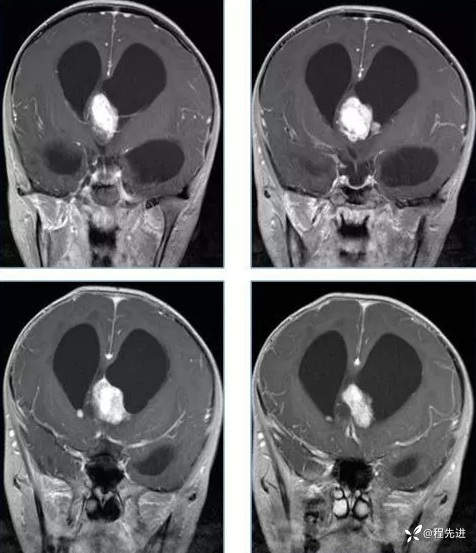

【神经】特别精彩病例|行走不稳2月余

患者性别:男

患者年龄:13岁

主诉:行走不稳2月余

现病史:2个月前患者无明显诱因下出现行走不稳,近期症状逐渐加重,站立不能。病程中患者无意识障碍,无头痛头晕,无明显恶心呕吐、视物旋转、耳鸣、眼球活动障碍等,无尿量增多、泌乳、口干等,体重无明显改变,睡眠可,食欲可,二便正常。

既往史:患者生后8个月和今年出现两次癫痫发作,持续时间不长

个人史:患者自幼失语,智力障碍

专科检查:右侧肢体肌力III-IV级,左侧肢体肌力IV级,肌张力下降